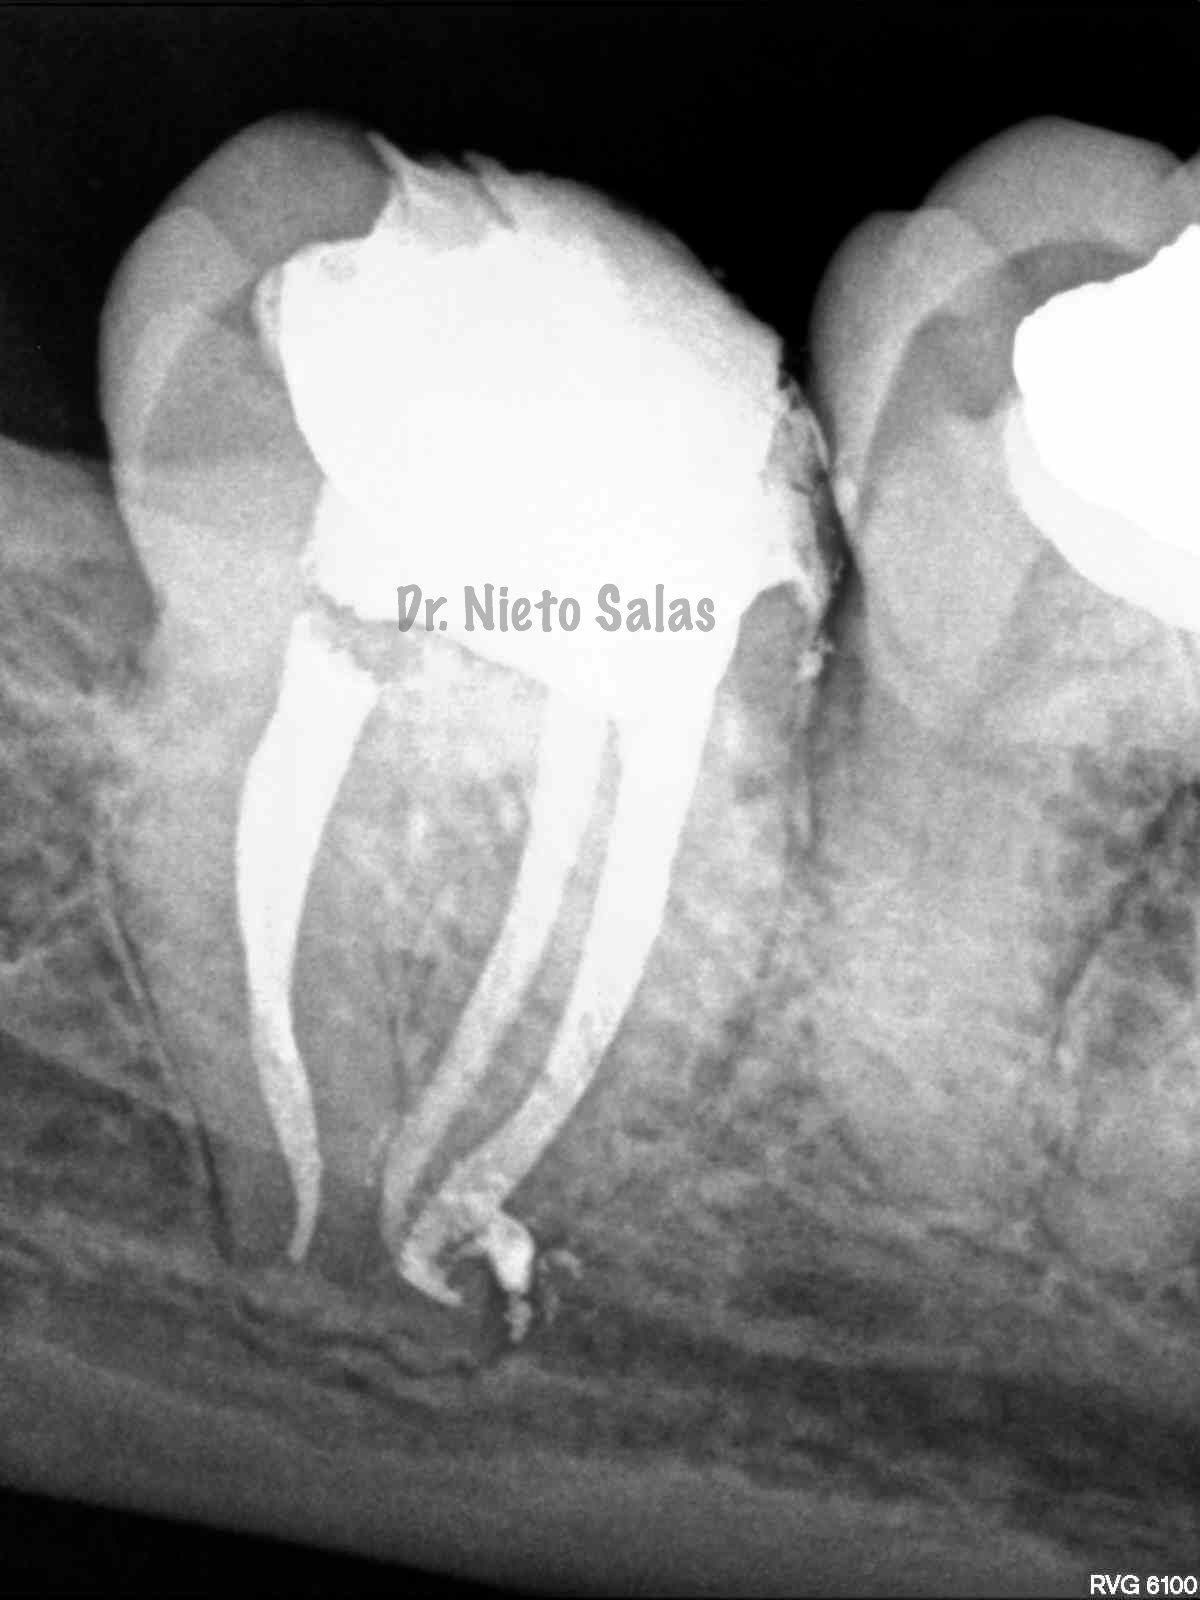

Así pues quedaría el sellado hermético y tridimensional:

La otra pieza, el 3.7, se instrumentó con sistema Protaper y obturación con Ola continua de Calor y un back-filling con la pistola Obtura II.

(buscamos siempre algún conducto lateral, para intentar asegurarnos de su limpieza)